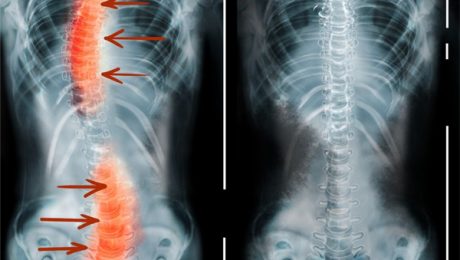

Что такое деформация позвоночника? Методы лечения